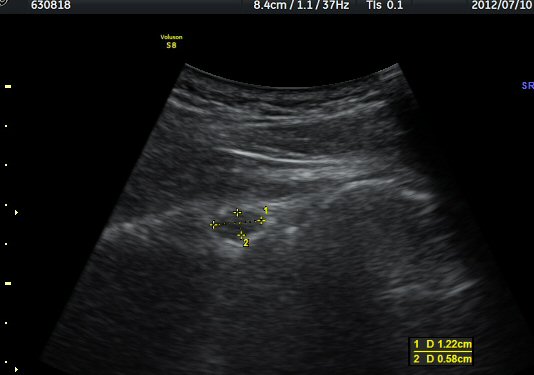

ÈíÀÎ 14ÀÏ ÈÄ ÃÊÀ½ÆÄ°Ë»ç¿¡¼­ ¾à°£ÀÇ ³¶Á¾ Å©±â °¨¼Ò°¡ °üÂûµÈ´Ù(±×¸² 7, 8)